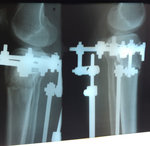

рентген в 20 дней после операции.